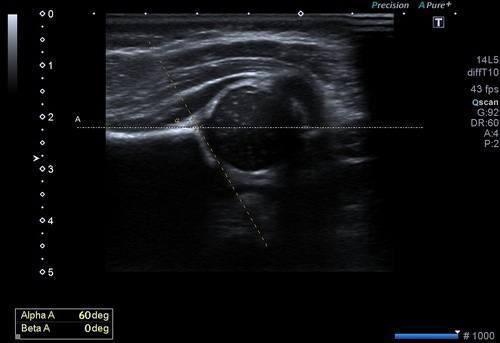

Bu inceleme de amaç her iki kalça eklemini oluşturan kemik yapıların, eklem ilişkilerinin ve kemik açılarının ölçülmesidir. Bu ölçümler ile kalça gelişiminin normal olduğu, yavaş olup düzelme eğilimi olacağı ya da gelişim geriliği olduğu saptanır. Bu ölçümlerin optimizasyonu için uluslararası bir sınıflama sistemi kullanılır.